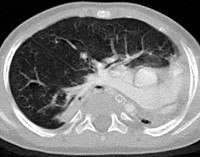

На рентгенограмме легких видно смещение средостения к больной стороне. В верхних отделах пораженного гемиторакса имеется участок нормальной ткани легкого, что может привести к ошибочному диагнозу. В целях дифференциальной диагностики этого дефекта с гидротораксом, ателектазом или диафрагмальной грыжей выполняется сканер грудной клетки. Контраст трахеобронхиального дерева во время бронхографии позволяет отличить легочную аплазию от агенеза. Ангиопульмонография выявляет отсутствие легочных сосудов.